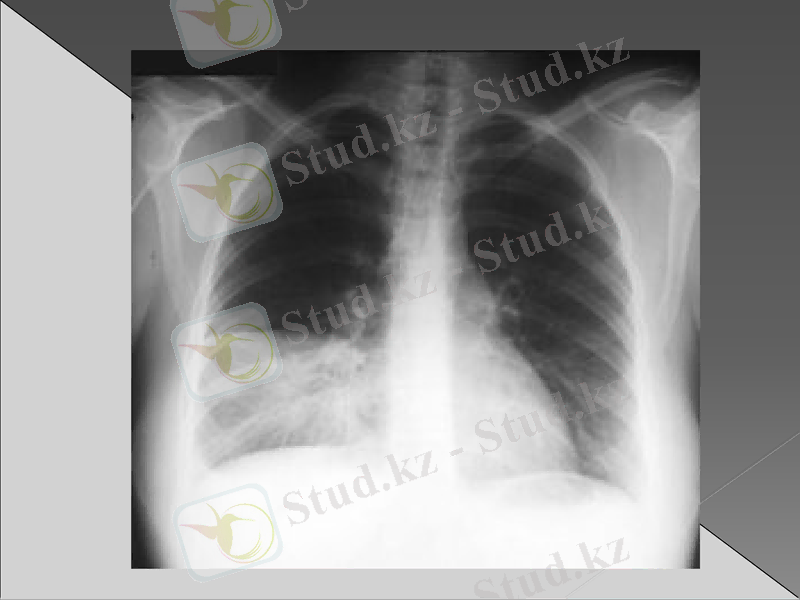

Рентгенография : инфильтрация немесе қараю зоналары (пневмонияның түріне байланысты өкпе тінінің зақымдалуы)

Рентгендік зерттеуде бірінші күні айқын көрінетін инфильтрациялық өзгерістер болмайды. Бұл кезде әрең байқалатын вуаль тәрізді нәзік көлеңкелену болуы мүмкін. Оның интенсивтілі біртіндеп күшейіп нағыз шыңына 5- тәулікте жетеді. Қан анализінде лейкоцитоз 15-30х 10/л дейін көбейеді. Лейко формулада нейтрофилдердің жетілмеген жас түрі көбейеді. ЭТЖ жоғарылайды. Сонымен бірге қанда қабынудың биохимиялық белгілері анықталады. Альфа және гамма глобулиндердің, фибриногеннің жоғарылауы, С реактивті белоктің пайда болуы. Қақырықта белоктің, фибриннің, эритроциттердің, лейкоциттердің мөлшері көп. Қақырық жағындысында қоздырғыш табылады.